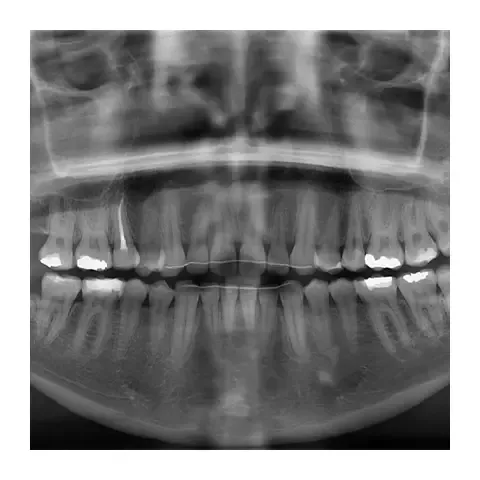

Paradontologija

Naš iskusni tim pruža sveobuhvatne dijagnostičke i terapijske metode za liječenje parodontalnih problema. Kombinujemo skaling, lasersku terapiju, te rekonstrukciju koštanog tkiva kako bismo zaštitili Vaš osmijeh od dugoročnih posljedica., nudimo individualizirane pristupe kako bismo zaustavili daljnje probleme i očuvali zdrave desni. Zdravi desni su osnov za zdrav i savršen osmjeh.

Ortodoncija

Naš ortodontski tretman ima za cilj postizanje usklađenog osmijeha. Koristimo najnovije tehnike i aparate kako bismo ispravili nepravilnosti zagriza i položaja zuba. Naši tretmani uključuju klasične aparatiće bilo mobilne ili fiksne za preciznu korekciju, te prozirne Invisalign tretmane za diskretnu terapiju.